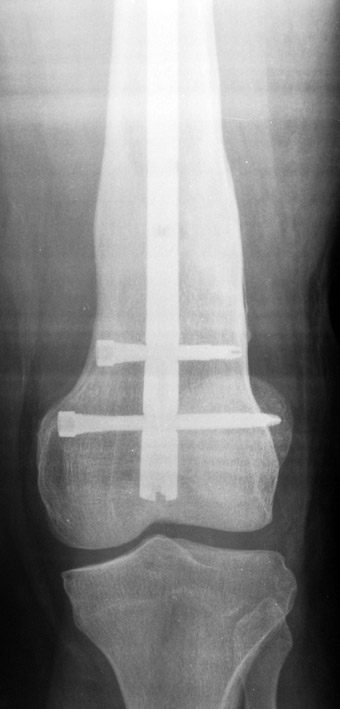

3. POSTTRAUMATIC LOWER LIMB SHORTNESS (MALUNION)

This type of shortness occurs after a fracture heals in a shortened position. Most cases are seen in adults and can be treated with one lengthening operation. Additional deformities can be corrected simultaneously. Most of these cases can be treated with lengthening over nail or just corrections and intramedullary nailing.